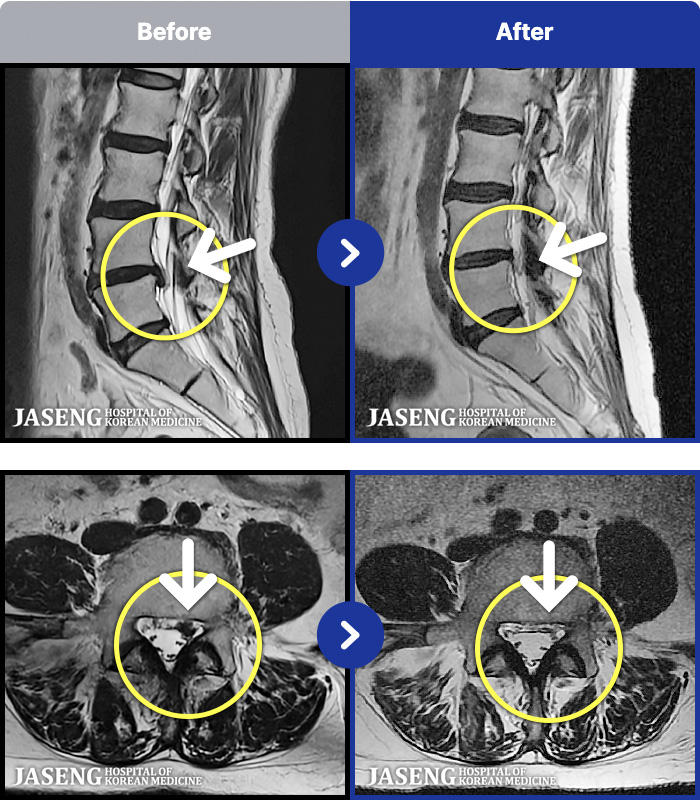

[Կñ:25.02.14~25.10.04]

[_㸮ũ] кο ٸ ٸ ٷϷ Ÿ.

No.51

ȸ 34

2026.01.06